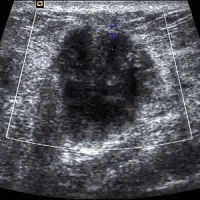

A research team from the Eindhoven University of Technology has recently developed a contrast-enhanced, ultrasound imaging method, which enables dynamic contrast specific ultrasound tomography (DCS-UST), in order to offer a breast-friendly and safer alternative to mammography.

The regular screening method for detecting breast cancer, the mammogram, is unpleasant, as it requires the breast to be squeezed tight. Moreover, it can be a contributor to the onset of cancer. More than two-thirds of the cases where a worrying anomaly is found on the X-ray images are false positives. Scientists thus seek alternatives in order to reduce or even eliminate such issues. Libertario Demi and colleagues, of UT Eindhoven, have developed a new technology in which the patient lies on a table and the breast hangs freely in a bowl. The method is known as ‘cumulative phase delay imaging (CPDI)’ and uses special echography, i.e. inaudible sound waves, to create a 3D image of the breast. The researchers expect that the rates of false positives will be much lower, as the technique generates images in which any tumour is clearly identifiable.

CPDI will lead to “a more practical, faster, and less operator-dependent imaging procedure compared to standard echo-contrast, while preserving accurate imaging of contrast kinetics.” Moreover, it can find clinical applications as a diagnostic method for breast cancer localisation. The researchers are planning to start performing preclinical studies once they put together an international, expert medical team. Application of the new technique is estimated to be ten years away. It is also expected that the new technology will probably operate in combination with other methods. The team’s future work will focus on “taking new measurements with a breast ultrasound computed tomography scanner on heterogeneous and more complex flow-phantoms, with the ultimate aim of transferring our technology to patients.”